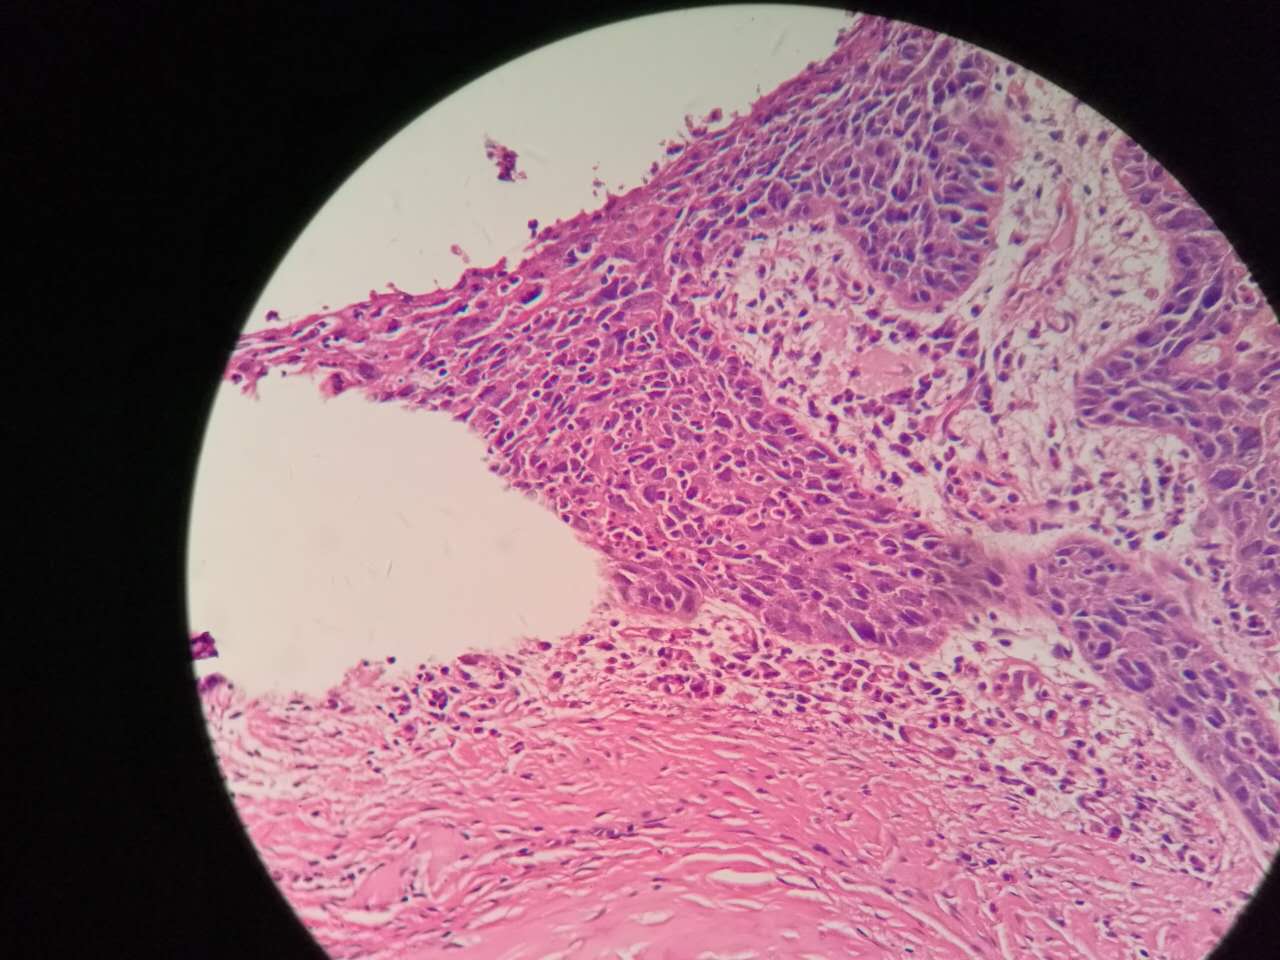

鳞癌

支气管鳞癌

复层排列,细胞有很多层

基底侧边界清楚

鳞癌生长,呈巢团状

巢团边界大多清楚

鳞癌是从支气管鳞化,异型增生,癌变,浸润,这么发展过来的。强调!

这个下面的软骨说明了是大气管,中央型

鳞癌组织学本质上没有周围型!

因为都是发生于支气管的,没有发生于肺泡和呼吸性细支气管的。

左手边有一点鳞癌,右手边有正常肺泡组织,中间有坏死物,这是为什么呢?

坏死物质渗出。

并且可以有吞噬,坏死物里常有血液成分

剖面多呈黄色

肿瘤周围不应是缺血,坏死一般在巢团内